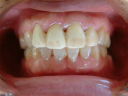

初診の状態とセット時の状態